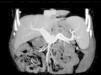

Doente do sexo masculino, 68 anos de idade, com antecedentes pessoais de hipertensão arterial, realizou tomografia computadorizada (TC) abdominopélvica em contexto de um episódio de insuficiência renal aguda relacionada com litíase renal, com o achado de possível massa cefalopancreática com cerca de 60×30mm. Na sequência, realizou angioTC que revelou um aneurisma fusiforme da veia porta, de diâmetro máximo de 37mm (figs. 1 e 2). Face a este achado, o doente foi encaminhado para consulta externa de angiologia e cirurgia vascular.